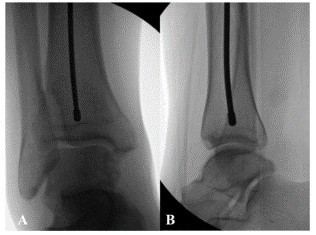

На рис. 11 показано положение проводника в костномозговой полости при рентгеноскопии С-дуги во фронтальном и латеральном положениях.

Рис. 12.AB Стопорные винты, вид на С-дугу; CD Запирающие винты с помощью электромагнитной компьютерной блокировки